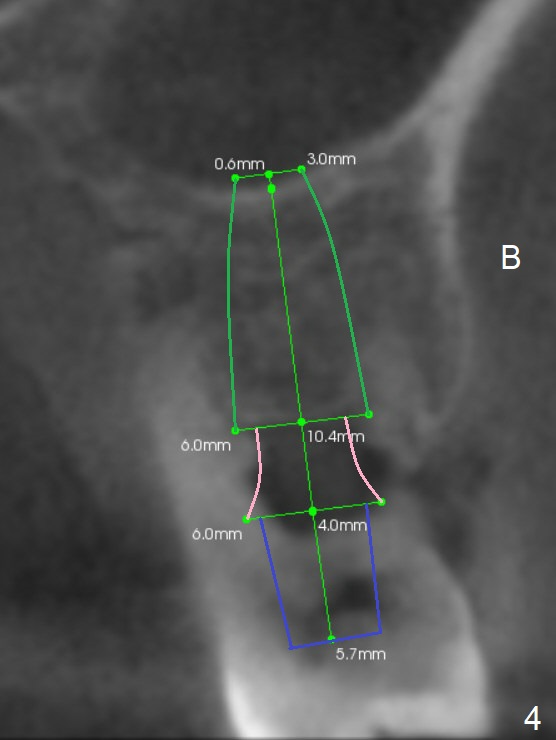

A 44-year-old man is a typical patient with chronic periodontitis (Fig.1).  Periimplantitis develops following immediate implant at #31 (Fig.2).  The symptom (bleeding) improves after bone graft and use of Water Pik.  Now the tooth #14 appears to be non-salvageable because of gingival hemorrhage and deep pockets after previous osseous surgery.  To prevent periimplantitis, an immediate implant does not need to be large or long.  It has to be placed deep, and in the middle of the native bone, surrounded by bone graft.  To facilitate wound healing, draw 3 tubes of blood for PRF.  One of them is processed for plug in case of sinus lift.  To prevent the buccal gingiva collapse, the buccal portion of the immediate provisional should extend into the socket.  If the gingiva is around 4 mm, use IBS implant (Fig.3,4).  Otherwise, a SM implant will be used after extraction (Clindamycin), since abutments have cuffs as long as 4.5 and 6 mm so that it is easy to place an implant as deep as possible.  Initial depth will be 9 mm (bone-level), followed by Magic Drill (5.3 mm, if possible) and Magic expanders (4.3x10 and 4.8x11 mm, bone density 26-300 units).